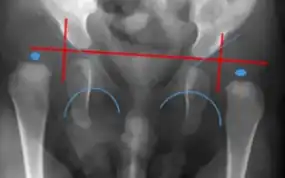

MRI- bilateral dislocation of hips, epiphyseal core (small arrow), and dysplastic acetabulum (large arrow) -

X-ray- dislocation of hips